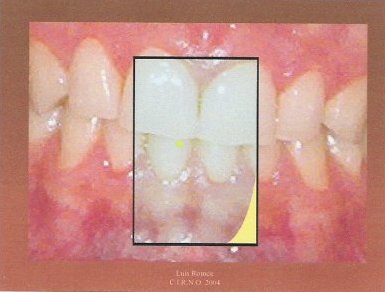

1.- Es conveniente adiestrar al paciente para que aprenda a realizar lateralidades izquierda y derecha desde su máxima intercuspidación. También es aconsejable poner un separador labial. Tras secar los incisivos superiores e inferiores con un rollo de algodón, marcamos un punto en la arcada inferior con el rotulador.

2.- Adherimos un trozo de papel celo a los incisivos superiores.